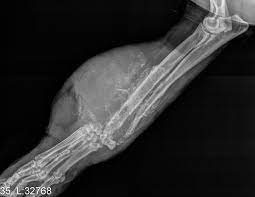

Primary bone tumors are uncommon in cats. Cancer is not just one entity—it is any process of uncontrolled cell growth. Chondrosarcoma of the bone in cats chondrosarcoma (csa) is a type of cancer that affects the cartilage of the body; Cancer cells that spread to the bone often affect these places: While a cancer diagnosis is emotionally devastating, some cancers are treatable if caught early. Fighting cancer in your pet starts with a trip to the vet at the first sign that things are not normal. Bone cancer is one of the most common types of cancer affecting cats. Attaches itself to the tissue under the skin in that area; For example, lymphoma affects the lymphatic system, while osteosarcoma affects bone. Cats are living longer, so of course we see more cancer in cats just because we see more cats. Read on to learn 10 facts about cancer in cats. An oral tumor is an abnormal growth of cells. There are many types of cancer in cats.

For example, lymphoma affects the lymphatic system, while osteosarcoma affects bone. Osteosarcoma, a tumor that affects the bones in your cat's legs, is one of the most frequently occurring cat cancers. Like humans, cancer in cats manifests as tumors. They can include swelling, lameness, and joint or bone pain. In older cats, the odds of. Learning about cancer helps prepare a family to deal with the diagnosis and treatment of their cat. Primary bone tumors are uncommon in cats. The most common sites of cancer in cats include the skin, the white blood cells (leukaemia and lymphoma), the mouth, the stomach and intestines and the mammary glands. Many cancer symptoms in cats are subtle and can be caused by another condition, but if you notice any of the following potential. Cancer in cats is the leading cause of death among cats. Limbs (upper arm and upper leg bones) pelvis (hipbones) rib cage. Cancer cells that spread from tumors in other parts of the body can form two main types of bone tumors: Chondrosarcoma of the bone is a fast spreading form of bone cancer, which can be life threatening if not diagnosed and treated early.